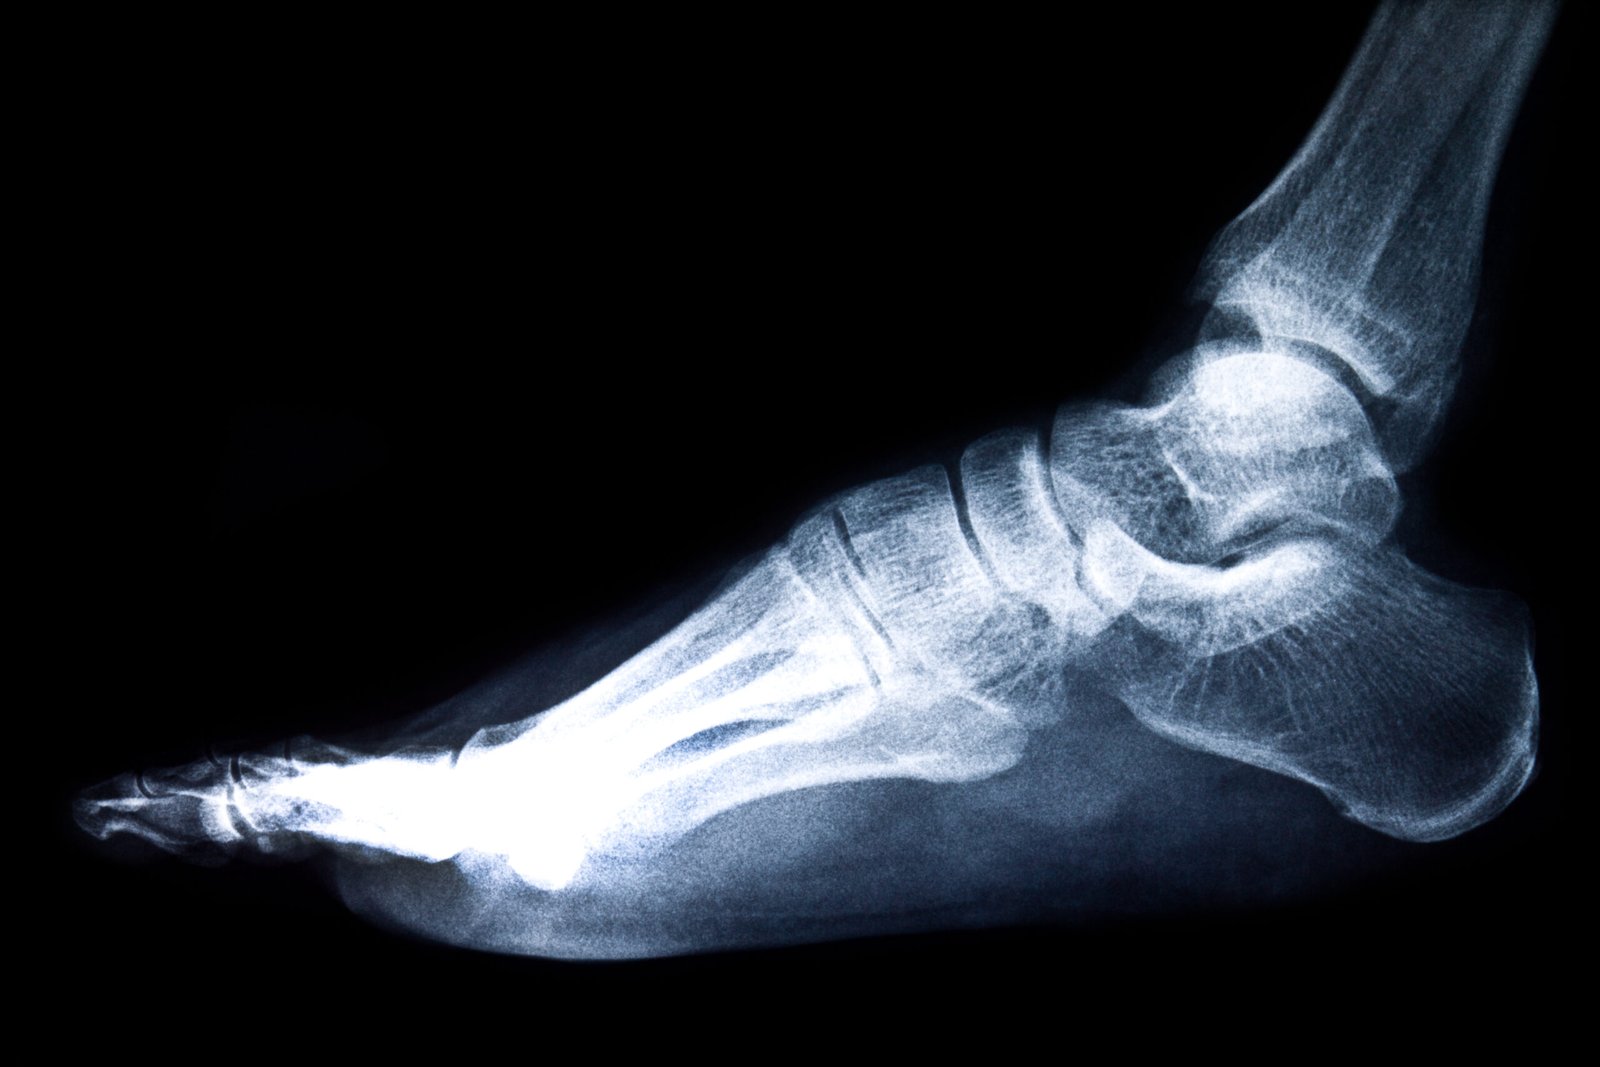

Understanding Foot & Ankle Anatomy

The foot and ankle region has 26 bones, 33 joints, and an abundance of ligaments and tendons. The important structures include the plantar fascia and the Achilles tendon, and the bursae. These elements integrate in joint support, locomotion, and balance. It can cause localized pain and impairment in functioning as a result of damage, overuse, or degeneration of any structure.